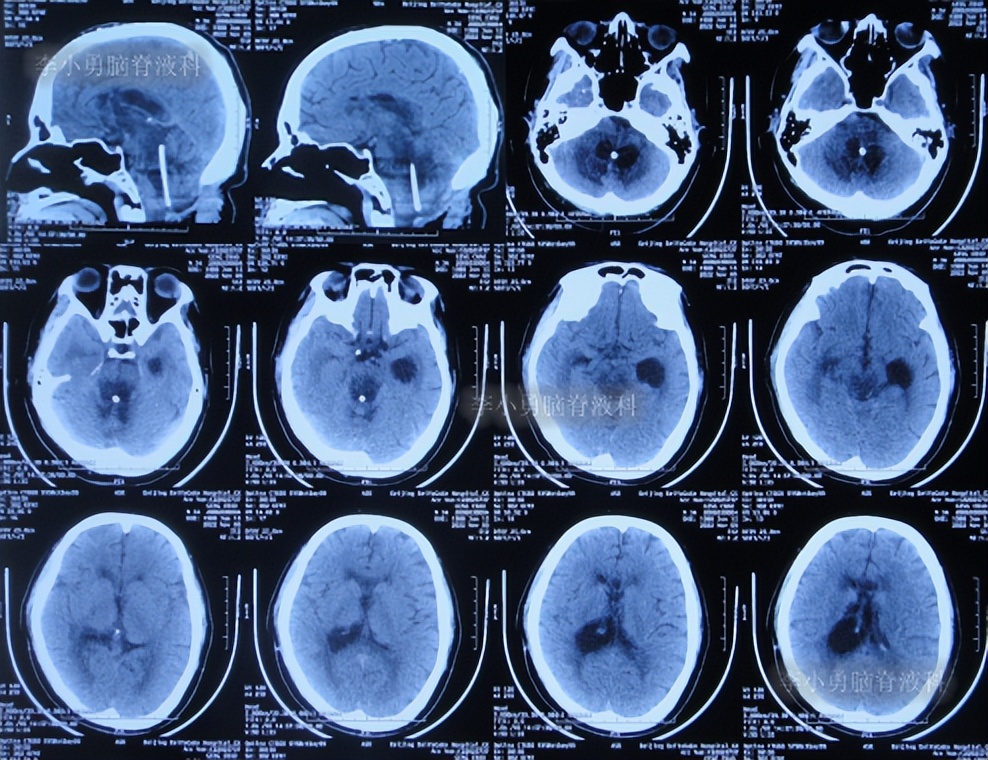

出院后1年半期间,仍时有视物重影的症状,并未给予处理,但到2019年9月27日(脑室腹腔分流术后1年零6个半月),出现头晕,恶心呕吐,视物重影加重,5天后因症状无缓解,就诊于当地的河南省临颍县某医院,查脑CT示脑积水(图-1);给予腰穿检查示颅内压力高220mmH2O。

图-1:2019年10月3日头颅CT